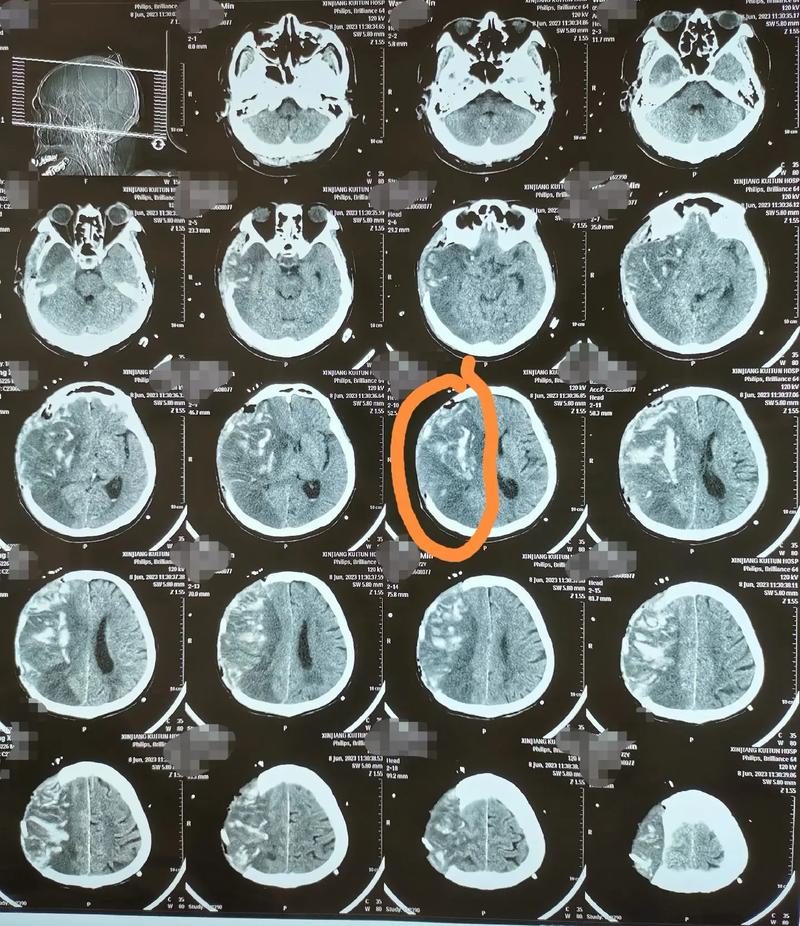

- 脑梗的严重程度和类型:是缺血性还是出血性?堵塞的是大血管还是小血管?梗死的部位和范围有多大?